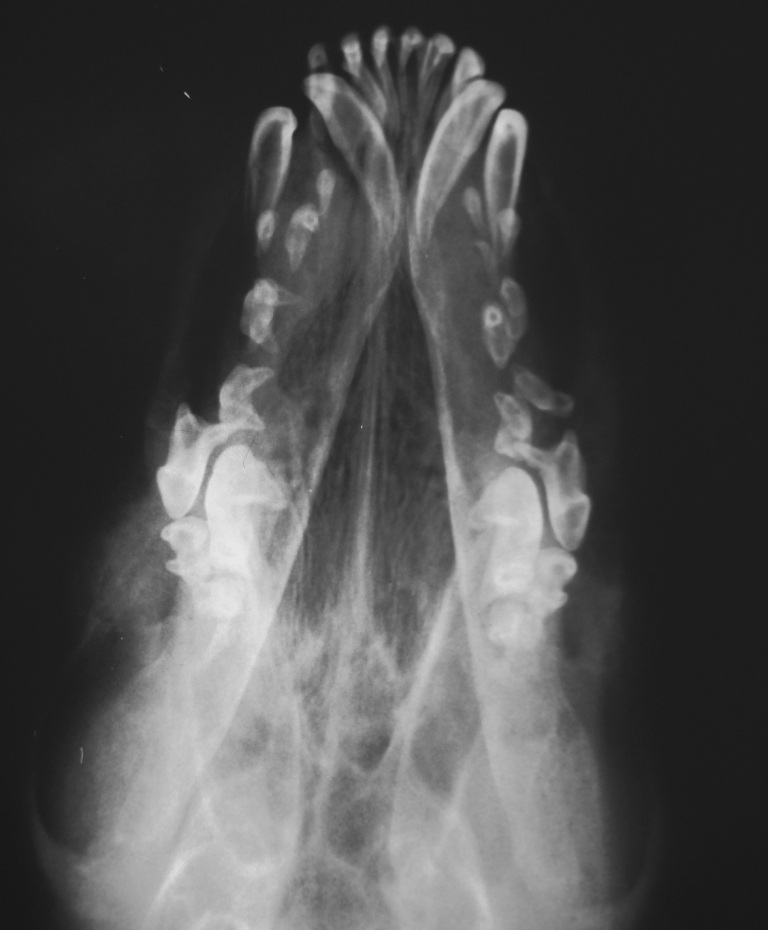

Dorsoventral view

.jpg)

On both views the bone has a radiolucent appearance. This is homogenous and does not appear to be

lytic or have permeative lysis. All the teeth are well mineralised and gives the appearance that

they are floating in air.